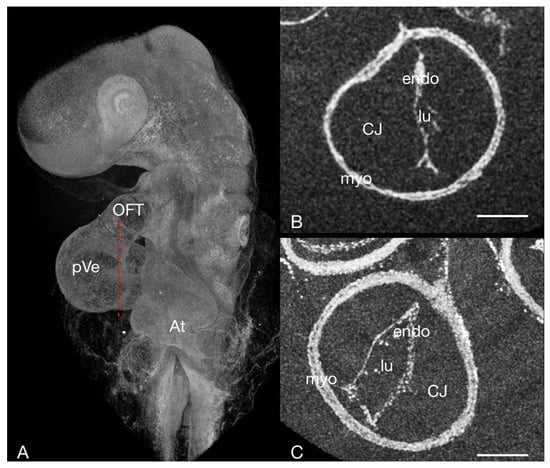

3.1. Embryo Preparation

3.2. Image Registration

3.3. Other Findings and Considerations

3.3.1. Staining Used

3.3.2. Using micro-CT for Doppler OCT Based CFD Model Validation